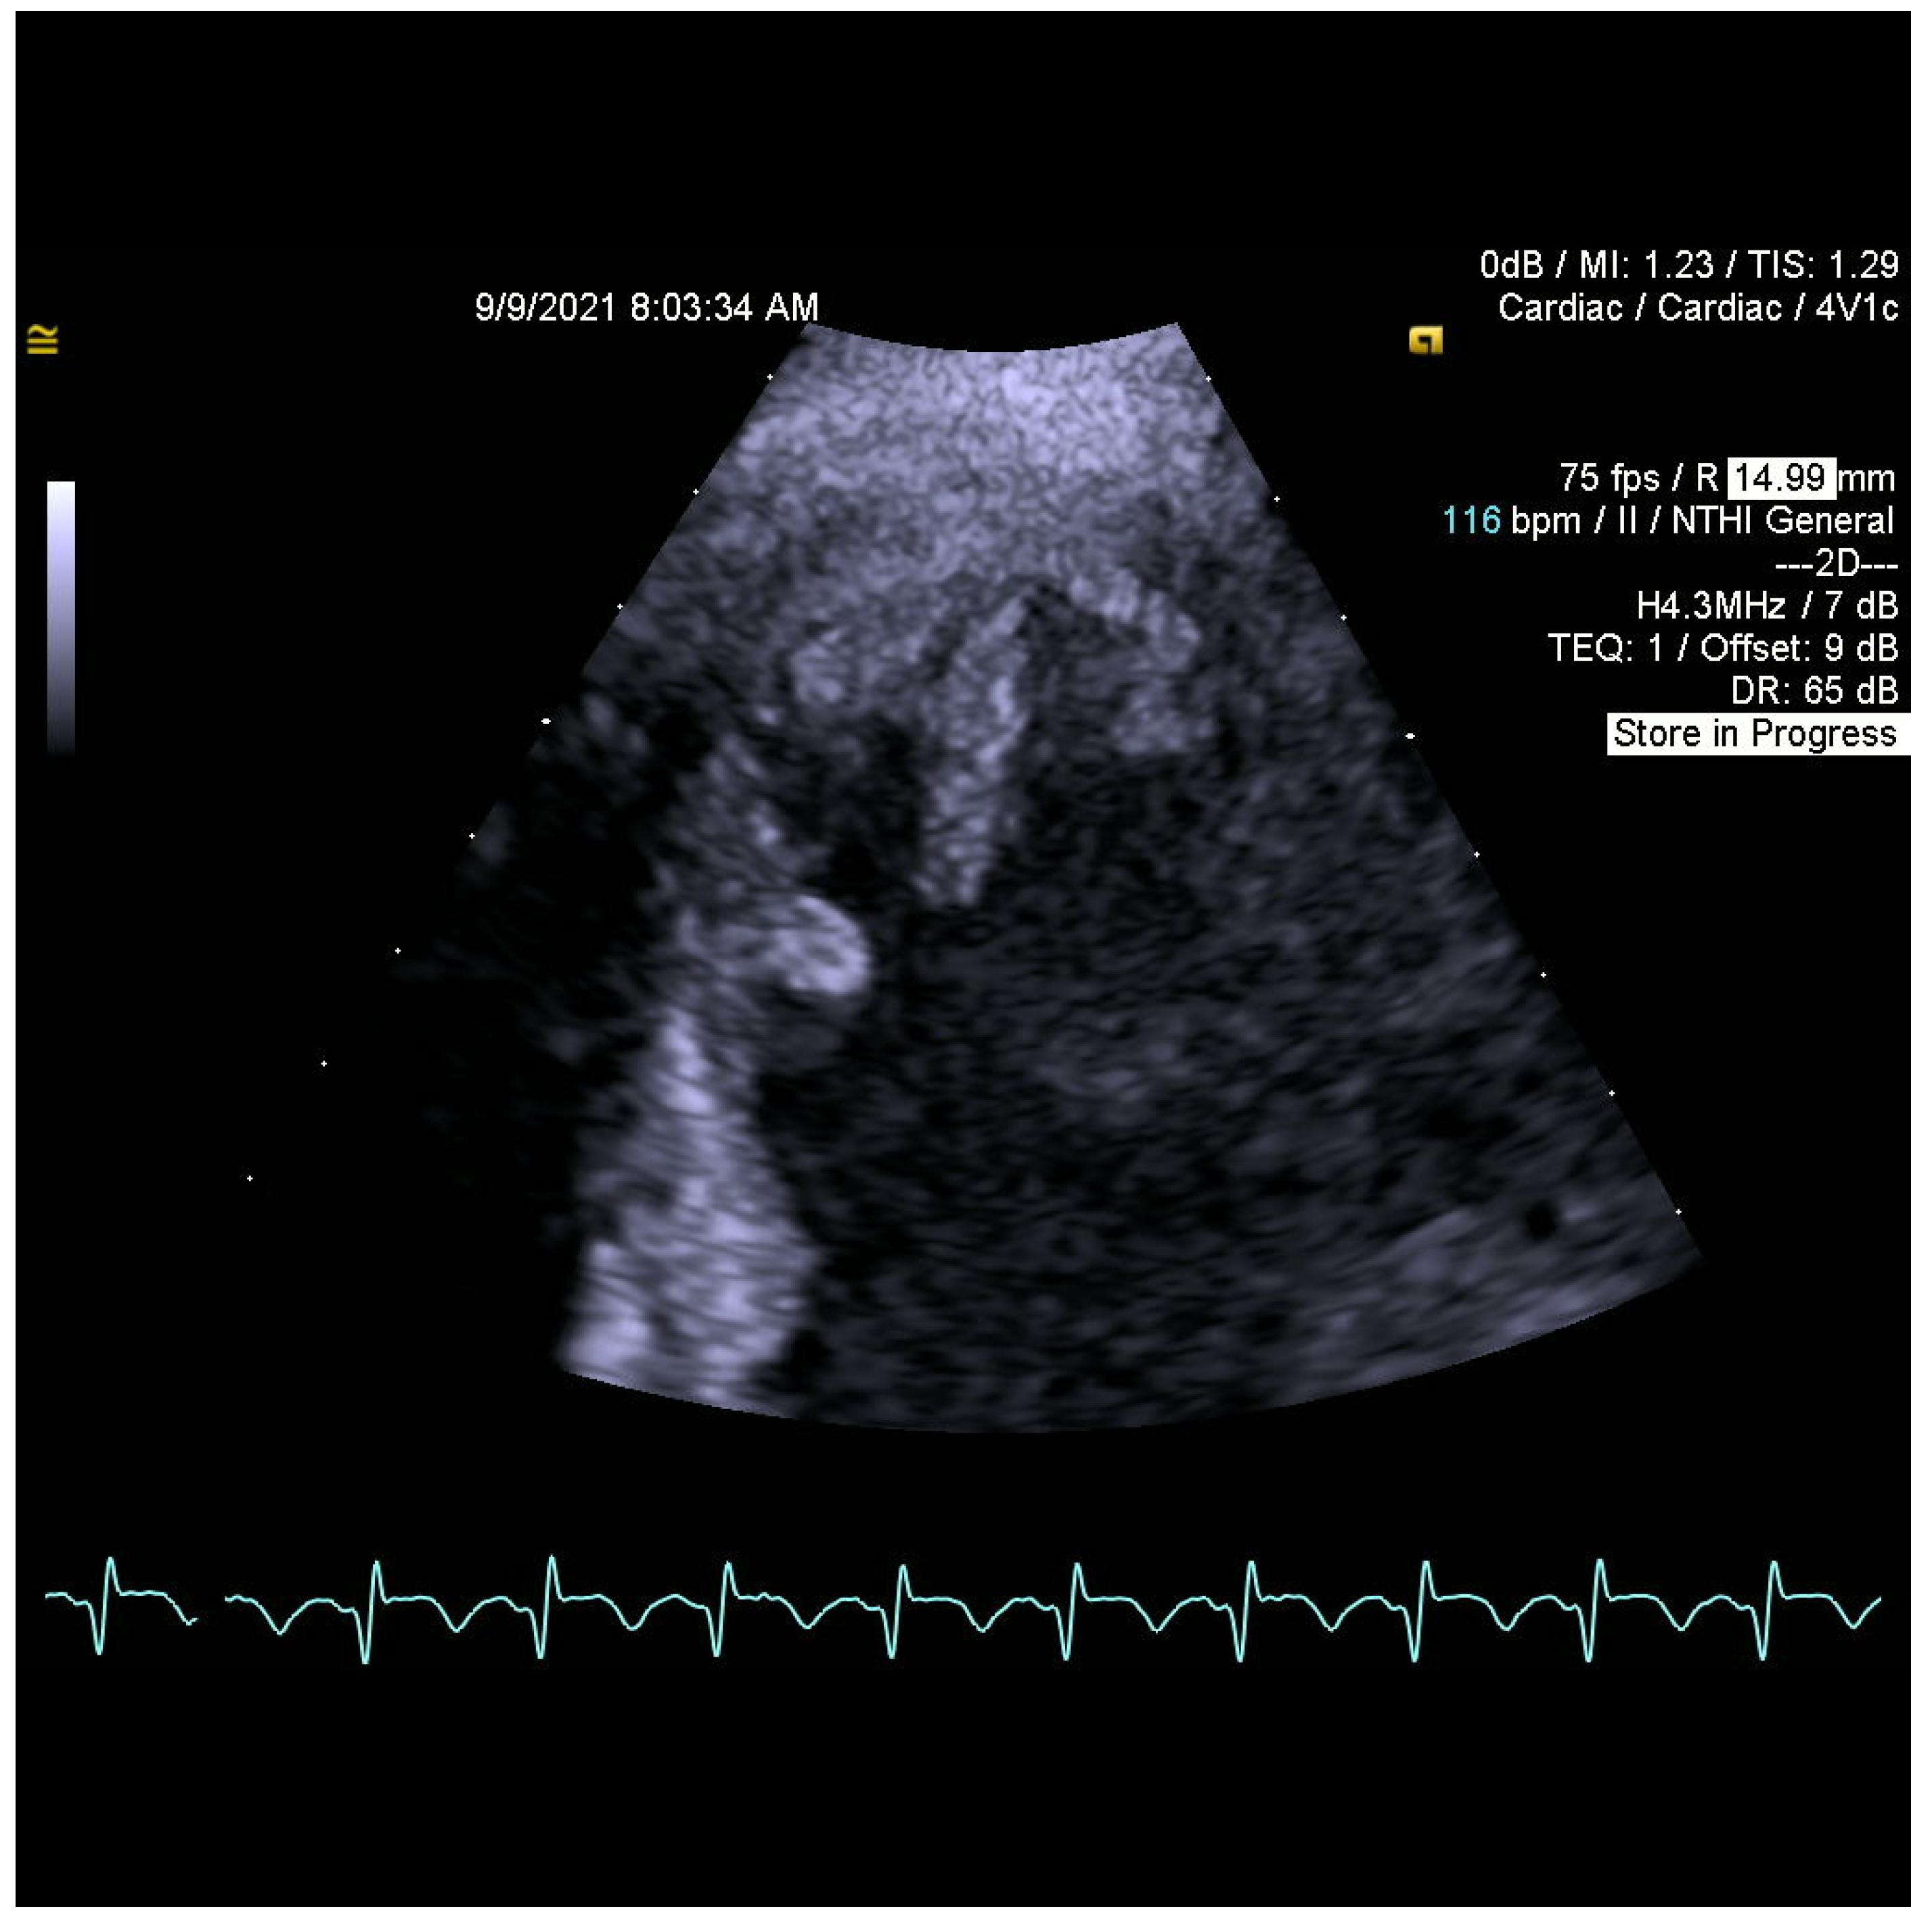

2. Case Report